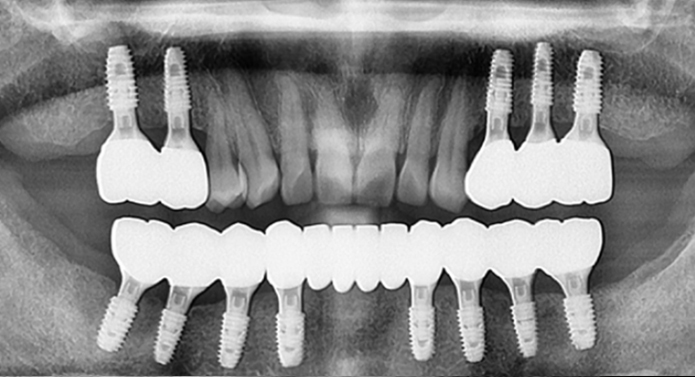

전체 임플란트는 상·하악 전체 치아가 상실되었을 때, 디지털 정밀 진단 → 최소한의 심기 → 고정형 보철 연결을 통해 자연 치아 기능과 심미성을 회복하는 디지털 기술력 기반의 치료입니다.

골 상태가 좋지 않아도 빠르게 고정되는 특수 나사 디자인

습기에 반응하는 초친수성 표면으로 골세포의 부착과 골유착을 획기적으로 향상

발치즉시, 즉시 부하, 뼈 질이 약한 고령환자까지 다양한 조건에서도 우수한 안정성 확보

전 세계 70개국 이상에서 사용되는 프리미엄 브랜드 SCI 논문 다수, 임상 연구로 효과 입증